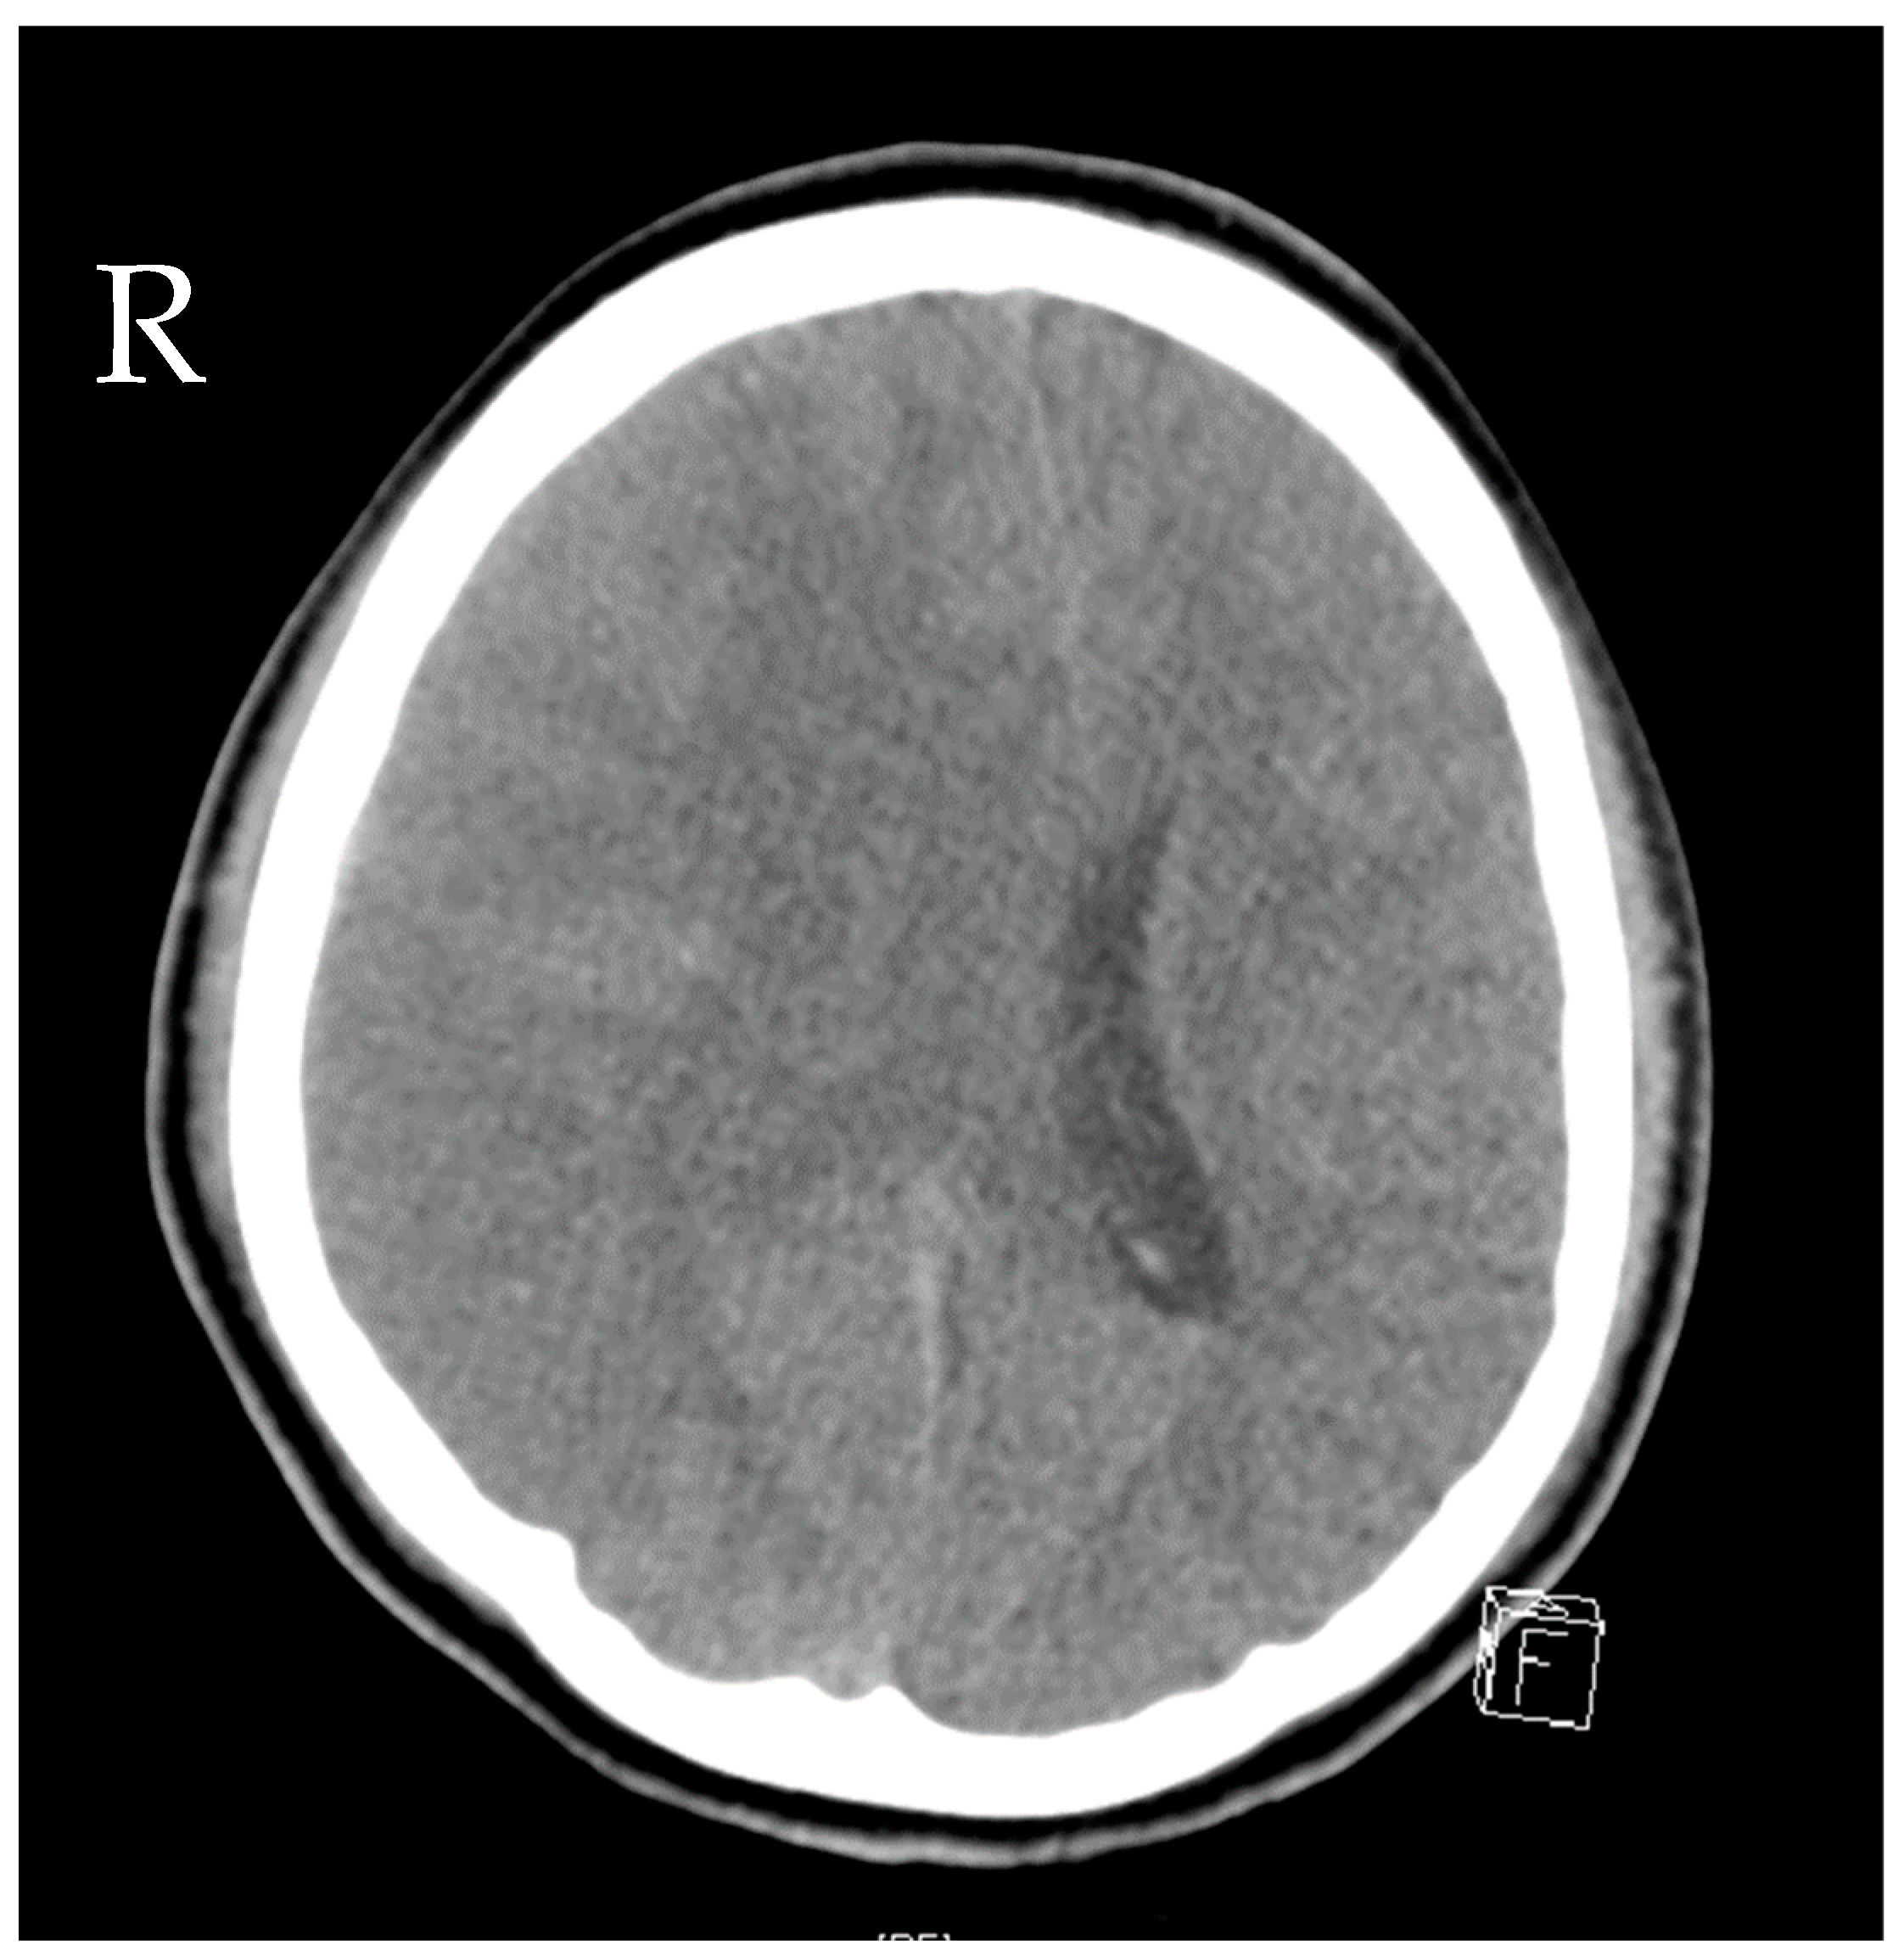

A 16-year-old girl was admitted to the emergency department after a car crash. By the time of admission, she was intubated, haemodynamically unstable and showed anisocoria. Haemodynamic instability was due to pneumothoraxes on both sides. Pleural drainage tubes were inserted immediately, and the circulation improved. A computed tomography scan showed polytrauma with severe craniocerebral injury and traumatic dissection of the right internal carotid artery. Moreover, there were severe bilateral pulmonary contusions, the laceration of the spleen and liver, a ruptured bladder with massive venous bleeding and an unstable pelvic fracture. Damage control surgery was performed subsequently with splenectomy, the opening of the bladder and the packing and temporary closure of the abdomen. The fractured pelvis was stabilized with an external fixator, and an intraventricular catheter was inserted to monitor the intracranial pressure (ICP). Only a few hours after the initial procedure, the patient presented with increasing ICP and dilated pupils on both sides. Another computed tomography scan revealed malignant, right hemispheric stroke due to the traumatic dissection with progressive cerebral oedema and signs of herniation (Figure 1). Decompressive craniectomy was conducted immediately to control the ICP. Postoperatively, the patient suffered multiple epileptic seizures and exhibited increasing blood sodium levels due to central diabetes insipidus.

Figure 1.

Computed tomography of the head showing cerebral oedema and signs of herniation.